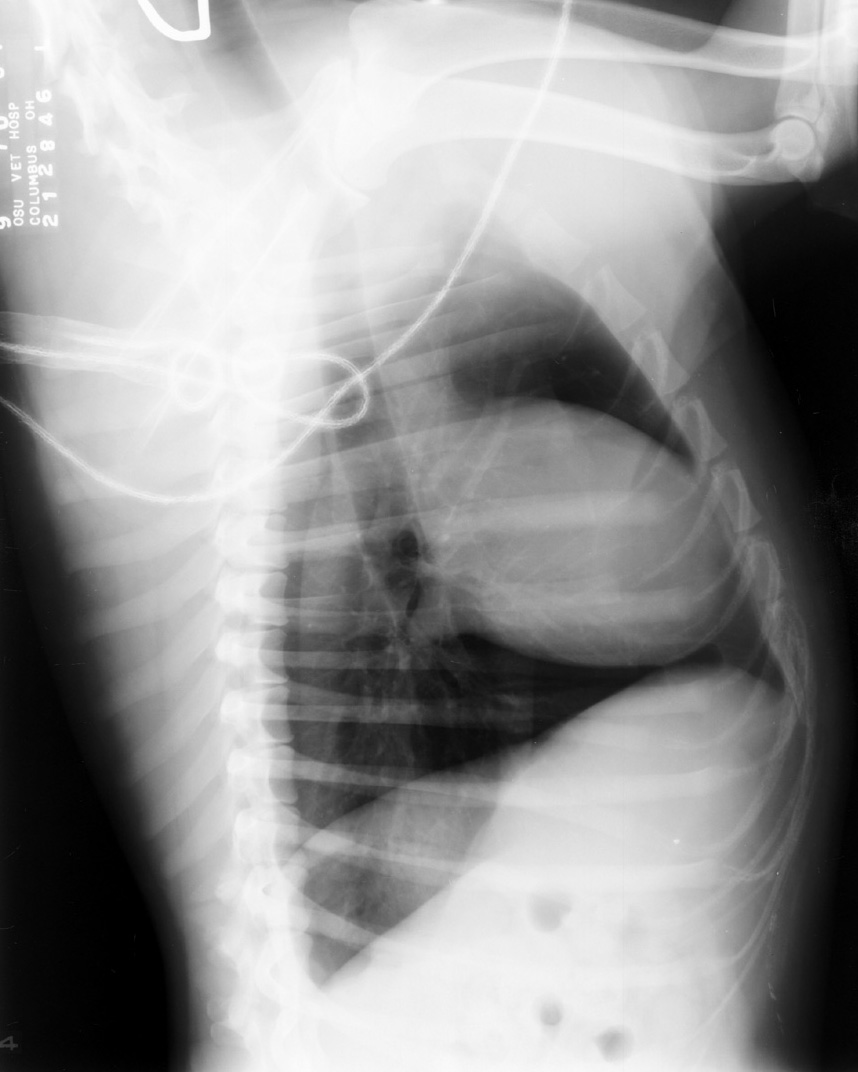

Rope Left on Animal